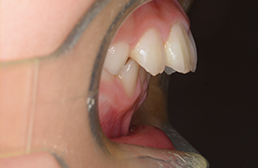

動的治療終了時

FP・IOP

批評・予后 本来であれば永久歯歯列完成後に本格矯正治療を行って良い症例だが、患者さん(保護者)の強い希望から早期治療にて改善を行った症例である。バイオネーターを夜間就寝中に使用して咬合誘導を行った結果、前歯の前突感は解消され比較的緊密な咬合は得られたように思う。